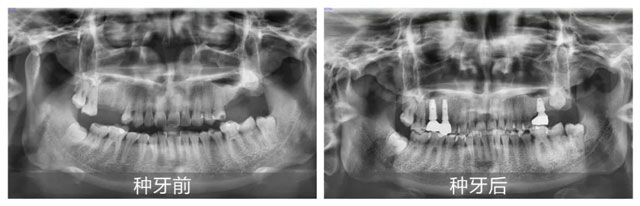

新橋口腔成都玉雙院區(qū)的口腔修復(fù)醫(yī)生代艷,為田女士進(jìn)行了全面且細(xì)致的面診。在獲取田女士詳細(xì)的體檢報(bào)告,并進(jìn)行全面綜合評(píng)估后,代艷醫(yī)療團(tuán)隊(duì)確認(rèn)其身體狀況適合接受手術(shù),于是果斷定制了多顆種植修復(fù)方案。當(dāng)天,田女士便順利完成了手術(shù)。 田女士回憶治療過程時(shí)說道:“這里的醫(yī)護(hù)人員太貼心了!治療結(jié)束后,他們有定期回訪,仔細(xì)叮囑治療后的各類注意事項(xiàng),時(shí)刻關(guān)注我的恢復(fù)情況,讓我心里特別踏實(shí)。”